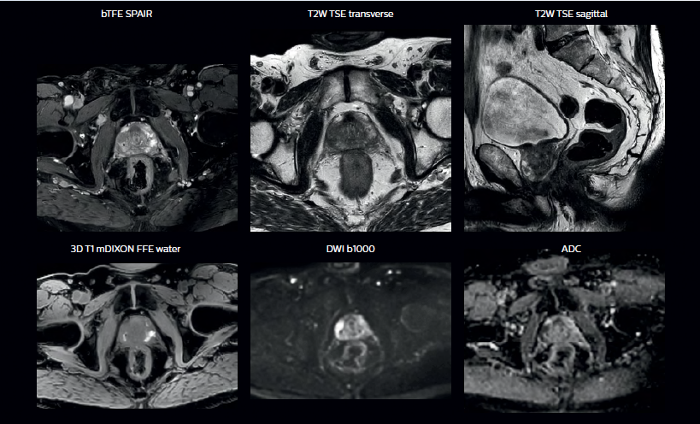

MRIは軟部組織の視覚化に優れており、幅広い画像コントラストに対応します。これにより、MRIは腫瘍の境界をより正確に描出できる強力なツールとなっています。放射線治療プロセスにおいて、標的体積の描出における不確実性が指摘されることがあります**。ターゲットとその近傍のリスク臓器をより良好に可視化することは、標的体積の描出を改善するための重要な因子です。また、MRIの役割は機能的イメージングにより広がりつつあり、ターゲットの評価と治療反応の両方の情報を提供します。

MRIはCTと比較して軟部組織のコントラストに優れているため、腫瘍の境界や近接する重要な構造をより明確に可視化できます。

さまざまなコントラスト情報の利用により、腫瘍の特徴や腫瘍の範囲について有益な情報が得られます。また、追加照射のストラテジーへの情報提供にもなります。

解剖学的情報に加え、MRIは腫瘍の検出と描出、および治療反応のモニタリングに有益な機能的情報提供することができます。

例えば、拡散強調画像(DWI)は腫瘍の水分子の移動(拡散)の制限を示すほか、リンパ節の識別にも用いられます。また、組織や病変部の見かけの拡散係数(ADC)の変化は、放射線治療に対する腫瘍の反応を予測するのに役立つ知見を提供することができます。